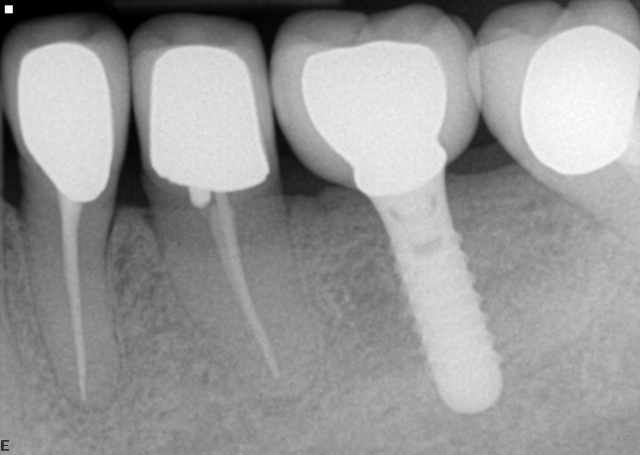

After everything checks out, you cement the restoration or torque it into place if it is screw-retained. A few years go by, and you check the patient during a regular hygiene appointment when you notice that the mesial proximal contact is open.

You know that the implant couldn’t have moved (since it is osseointegrated), so that must mean the teeth anterior to the implant restoration have moved. But where could they go? The lower anteriors are still coupled with the upper anteriors, preventing them from moving forward. So what is going on?

Believe it or not, the presence of diastemas developing around implant restorations is not that uncommon. The loss of interproximal contact between fixed implant restorations and adjacent natural teeth was evaluated in a 2010 paper from Koori and colleagues.1 Evaluation ranging from one to 123 months (10.5 years) showed that out of the 146 placed restorations, 43% developed an open interproximal contact, most commonly on the mesial. This paper shows that the most significant incidence of developing an open contact was in patients with an opposing dentition with natural teeth or implants, AND where the teeth adjacent to the implant restoration were non-vital and non-splinted.

What is the mechanism for the development of these open contacts? It is hypothesized that this results from mesial drift — wearing of the interproximal contacts as a result of attrition of the contacts over time.1, 2

Given that nearly half of the patients in this study developed an open interproximal contact, we must continually monitor our implant patients at follow-up visits; an open contact may induce food impaction and have an adverse effect on the peri-implant bone/soft tissue. When it is present, either the implant restoration needs to be replaced or the tooth anterior must be restored to close the contact. The downside is that if the contact opens once, there is always the chance it can open again in the future if you wait long enough.